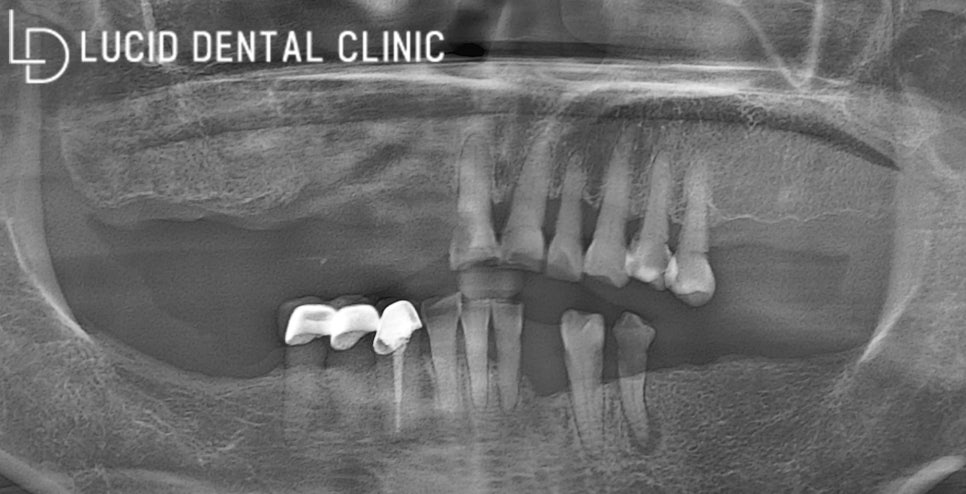

아래 보이는 건 환자의 구강 전체를

촬영한 파노라마 방사선 사진인데요.

저작 기능을 위주로 사용하는

어금니가 남아있지 않았고,

상악(위턱) 작은 어금니와

전치부만이 남아있었습니다.

문제는 그것뿐만 아니라

치근단 병소까지 심하게

나타났다는 것인데요.

치아 변색뿐만 아니라

정출까지 심하게 나타나

이대로 계속 놔두게 되면

남은 자연치 보존이

어려워질 수 있습니다.